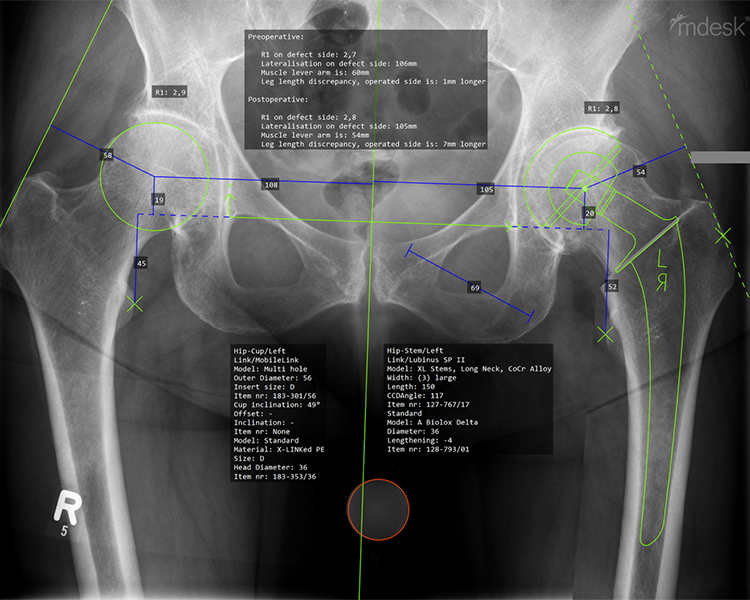

CAD-gestützte Planung

Nach meiner Überzeugung kann nicht jeder Patient mit einem einzigen Prothesenmodell erfolgreich versorgt werden. Daher arbeite ich seit vielen Jahren mit verschiedenen bewährten Prothesenmodellen, um nahezu jede individuelle Anatomie optimal abzubilden.

Nur durch diese maßgeschneiderte Auswahl können die Muskeln wieder in ihrer natürlichen Funktion arbeiten,  die Voraussetzung für schmerzfreies Gehen und bestmögliche Lebensqualität.

Die computergestützte (CAD) Planung ermöglicht es, jeden Eingriff präzise zu simulieren und die optimale Prothese für Ihre individuelle Anatomie auszuwählen, für maximale Präzision und langfristig erfolgreiche Ergebnisse.

computergestützte OP-Planung für optimale Ergebnisse:

• Patientenspezifische Anatomieanalyse

• Präzise Implantatauswahl & -positionierung

• Simulation von Offset, Beinlänge & Gelenkzentrum

• Biomechanisch optimierte Rekonstruktion